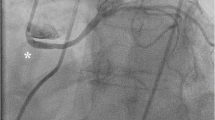

The Angelini/Cheong sign. In a right anterior oblique projection, the plane crosses the aortic root and pulmonary valves, at the level of maximal obstruction by compression of the intramural right coronary artery (in this case, the ratio of the longitudinal versus transverse diameters is about 3:1, indicating stenosis, probably severe in nature). AV, aortic valve; PV, pulmonary valve. Black arrow = compressed intramural right coronary artery

R-ACAOS-IM as seen by catheter angiography (above) and by IVUS (below). Top row: The 3 angiographic frames illustrate that the ostium appears to be enlarged in the left anterior oblique (left side, arrowhead) but severely stenotic in the right anterior oblique projection (center: arrows = proximal stenosis, asterisk = ostium); after ostial stent deployment, the ostium appears to have gained a normal size (right). Bottom row: In diastole (left panel), in systole (center panel), and at a distal reference (right panel). The stenosis was calculated as 79% in systole and 50% in diastole. The short diameter was 0.9 mm in systole and 1.9 mm in diastole, signs of severe stenosis. The outline of the cross-sectional media layer areas is shown as having a mean diameter of 4.0 mm. Dotted line = internal elastic media layer

In adolescents or adults, s-MRI is the ideal testing tool. This test can yield a consistently specific diagnosis of high-risk CAA type, and it can be performed quickly and reliably without side effects or discomfort [9••]. Moreover, the test does not require potentially dangerous radiation (ionizing) or the administration of intravenous medicines and contrast, and the data can be acquired in 10–15 min [9••]. Specialized reading of the data can be obtained easily, possibly even by remote analysis at specialized centers. The basic interpretation technique for CAAs involves clarifying the location of the aortic valve commissures (and sinuses), the coronary ostia, and the proximal course of the ectopic coronary artery. Only the intramural aortic course is associated with some degree of stenosis, but the exact quantification of stenosis cannot be achieved by s-MRI (and by CCTA). In a screening context, CCTA imaging requires intravenous access and the use of ionizing radiation, contrast medium, beta-blockers, and occasional sedation. CCTA is more precise than s-MRI in confirming the anomalous origin, the proximal course, and the approximate severity of stenosis by using a cross-sectional image at the level of the aorto/pulmonary septum (anterior commissure of the aortic valve) that consists of the Angelini/Cheong sign (Fig. 2), which comprises the cross-sectional ratio between the long and short axes of the anomalous intramural artery; a ratio greater than 2:1 suggests significance [16].

Selective catheter angiography can be technically laborious and difficult in the presence of tangential and ectopic coronary origin. Special catheters have been recently developed that make the cannulation and backup support easier (for IVUS catheterization, stent PCI, besides angiography) [2]. In ACAOS, catheter angiography is primarily used for definitive imaging of the distal vessel (dominance coronary tree pattern and atherosclerotic burden). Ostial stenosis is generally poorly evaluated by catheter angiography [7••, 8•].

IVUS is a catheter-based procedure (Figs. 3 and 4) in which high-precision cross-sectional imaging of the coronary lumen is obtained by passing an ultrasound probe over a coronary catheter guidewire in a patient who has been transiently anticoagulated (typically with heparin). Obtaining this in vivo highly precise imaging is important because coronary stenosis in ACAOS-IM occurs in phasic fashion (present at baseline, with systolic worsening). In athletes, the concern is focused paradoxically on highly trained individuals (able to compete at very high heart rates and cardiac outputs) who participate in strenuous exercise and who are usually asymptomatic (by self-bias selection, in light of the fact that only asymptomatic athletes do sports). In cases with borderline severity, measuring the severity of coronary narrowing during simulated exertion may be useful. Currently, this study is indicated when the baseline resting stenosis is mild (< 50% in L-ACAOS-IM and < 55% in R-ACAOS-IM) and the clinical need to assess stenosis is important (the need to establish an indication for intervention or disqualification from competitive sports) [7••, 8•]. The severity of intramural CSA stenosis is calculated in reference to the distal extramural reference vessel (Figs. 3 and 4). IVUS can also confirm with certainty that the stenosis in R- or L-ACAOS-IM is always “intramurally, inside the aortic tunica media”; the frequently purported mechanism of stenosis by inter-arterial coronary compression between aorta and pulmonary artery is never seen. Much of the discussion about inter-arterial course nomenclature has marred this field in cardiology and should be abandoned, based on the overwhelming evidence offered by IVUS. The only case of CAAs with an initially inter-arterial course, but without an intramural course, has an intraseptal (or infundibular) course, and it should not be considered inter-arterial (generally a benign variant) [7••].

In R-ACAOS-IM, the stenosis is always ostial, whereas in L-ACAOS-IM, the site of maximal narrowing can vary and can be seen at the ostium or at the mid-section or distal to the intramural section (Fig. 4). IVUS can establish the length of the intramural segment and the level of the intramural course with respect to the upper edge of the anterior commissure (important for surgical considerations).